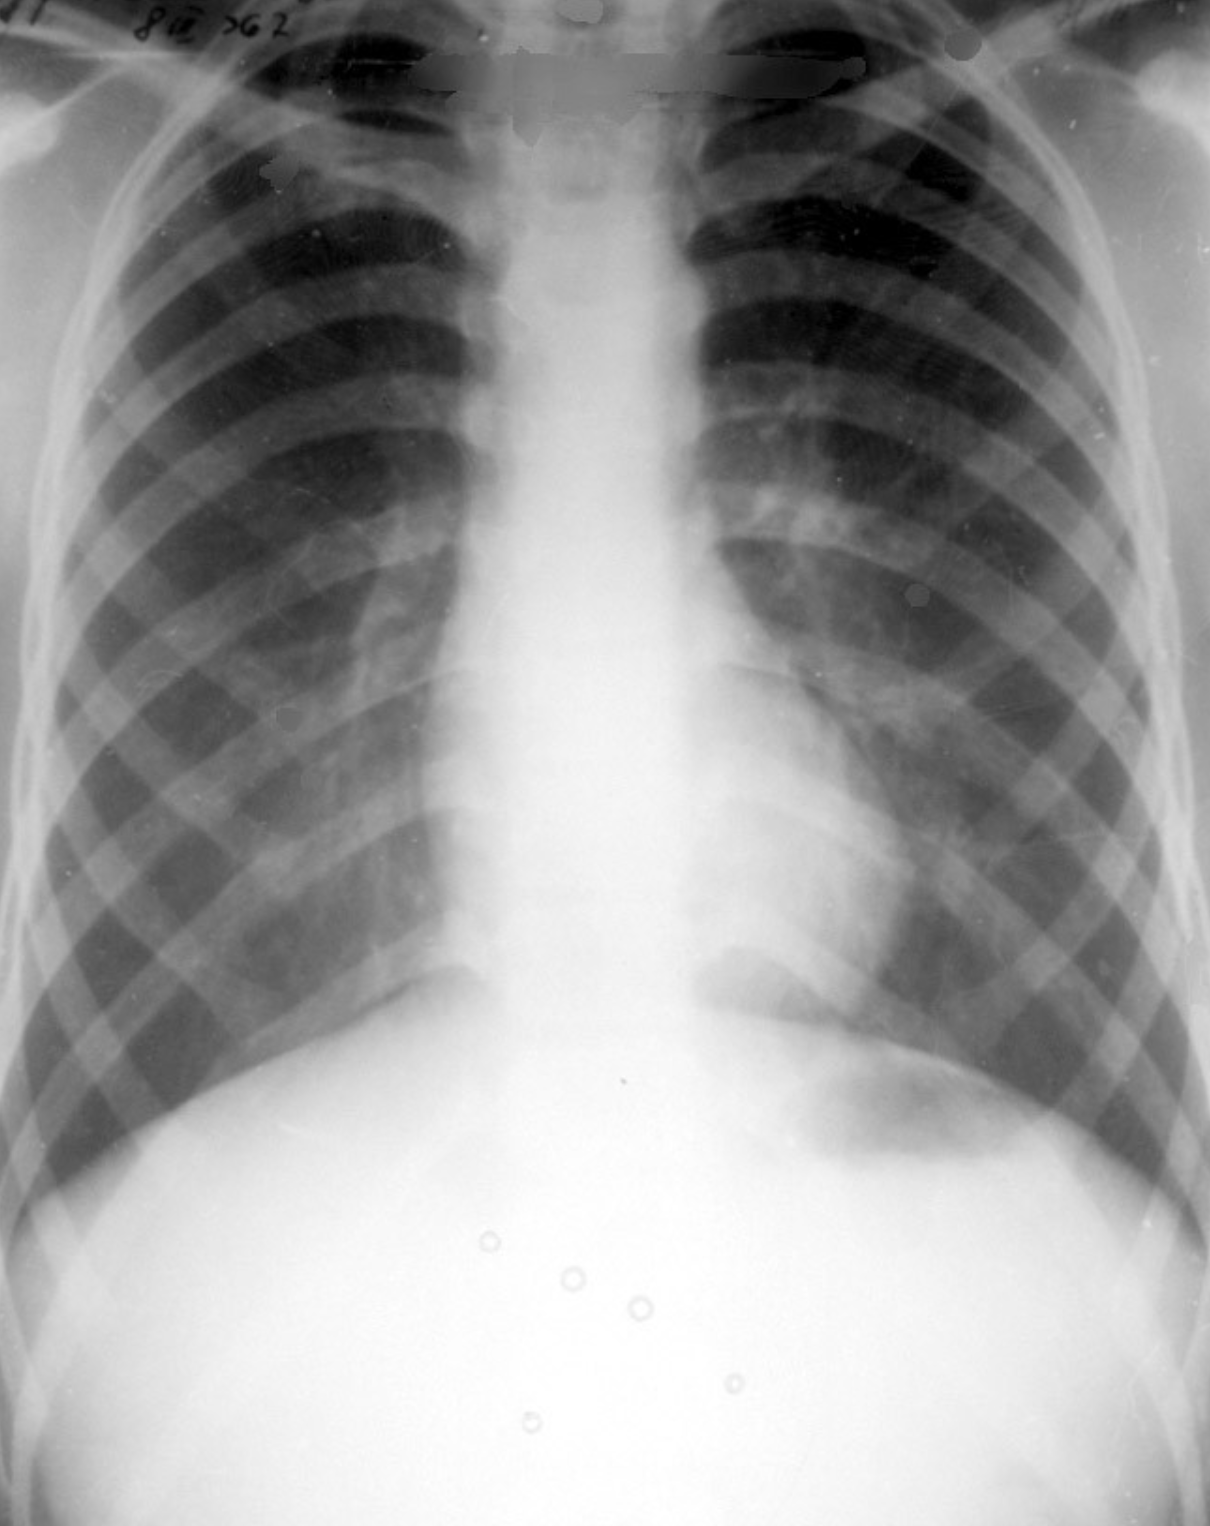

Pericardita exudativa/colectia pericardia - aspect RGR

- Pericardita exudativa (acumulare de lichid peste 50ml)

- modificarea formei cordului – disparitia arcurilor cardiace, cord in carafa sau plosca

- pulsatii cardiace absente sau reduse (radioscopie)

- desen pulmonar redus sau normal (se reduce intoarcerea venoasa)

- Unghi cardio-frenic sub 90 de grade (ascutit)

- cantitativ:

- mica sub 200ml (nu se vede radiologic, se vede ecografic pe conturul posterior si pe conturul stang al cordului)

- medie 200-500 ml

- mare peste 500ml

- Dg diferential cu afectiunile miocardice

Pericardita exudativa in cantitate mica

- Water bottle (plosca de apa)

Pericardita exudativa in cantitate mare